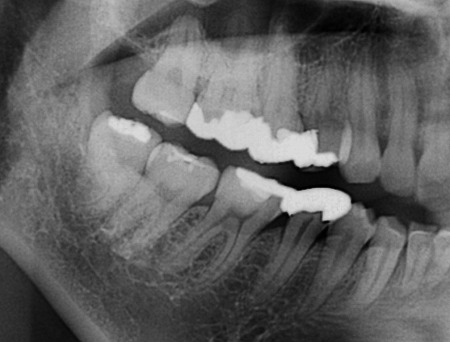

色々と先生によって意見が分かれる所ではありますが、私はあまり積極的には抜かない事が多いです。

基本的に、腫れた事のない無症状のものは抜きません。一度腫れるとまた腫れる可能性が有りますので、抜く事をお勧めします。しかし、あとは患者様ご自身の判断で良いと思います。